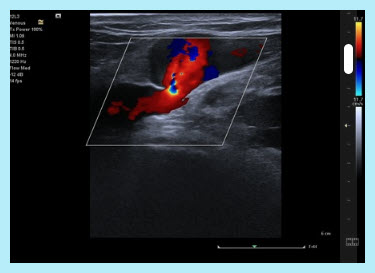

Manual distal compression or automated rapid cuff inflation/deflation devices must be used as provocative maneuvers assessing valvular function to determine competency or reflux in all lower extremity venous segments evaluated.